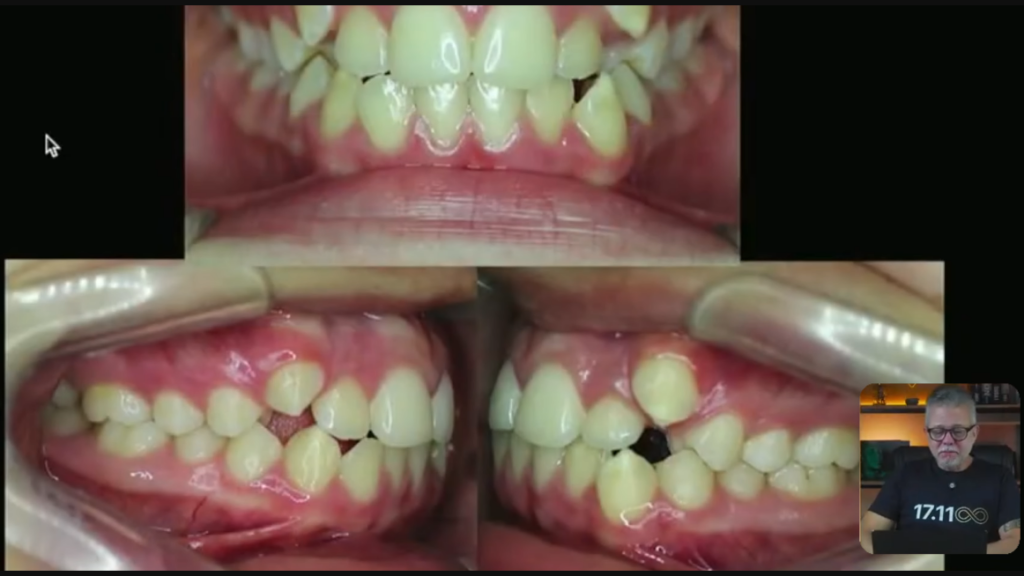

O diagnóstico dessa paciente aqui é uma paciente dólico-facial. Ela tem um sorriso gengivoso que não tem conserto sem cirurgia ortognática.

Então, a paciente dólico, você pode observar na face dela, ela não tem grandes assimetrias.

Então, essa nossa paciente, ela tem todo esse apinhamento.

Vocês estão vendo que ela está de classe 1, do lado direito e do lado esquerdo?

Quando você tem uma paciente de classe 1 dos dois lados e você tem bastante apinhamento, você pode até pensar em tirar pré-molares.